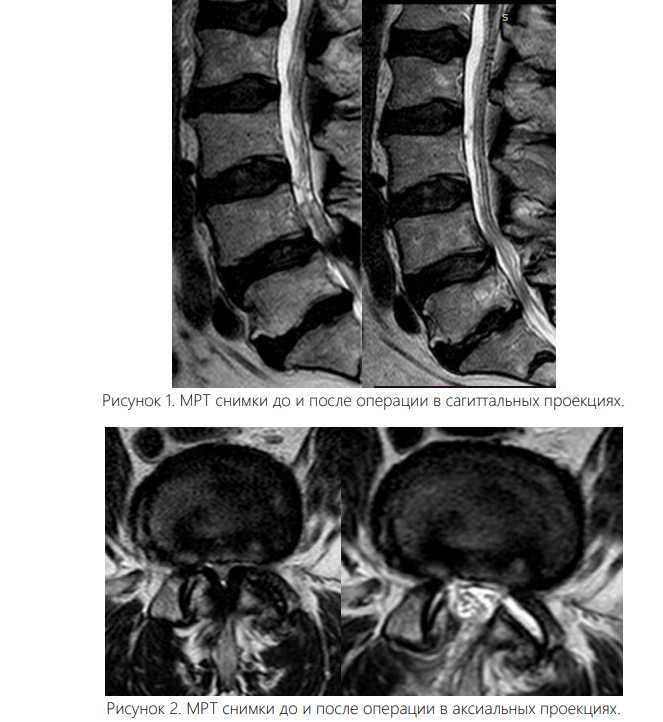

Вмешательство осуществляли под интубационным наркозом. Все операции были выполнены одним и тем же хирургом. Пациента укладывали на живот с подложенными мягкими валиками под грудной клеткой и тазом, уменьшая таким образом внутрибрюшное давление и степень интраоперационного кровотечения. Уровень вмешательства определяли с помощью интраоперационных флюороскопии. Срединный кожный разрез длиной 0,7 см располагался точно над уровнем соответствующего межпозвонкового диска. Зона ламинотомии в краниальном направлении простиралась до области прикрепления желтой связки к дуге вышележащего позвонка, а каудально резекция дуги нижележащего позвонка составляла не более 2-3 мм для адекватного обнажения ножки позвонка. Проведен анализ результатов хирургического лечения 102 больных со стенозом поясничного отдела позвоночника, находившихся в отделении вертебрологии Республиканском центре травматологии и ортопедии Узбекистана в период с 2020 по 2024 год. Для определения размера позвоночного канала, а также степени дегенеративного стеноза в позвоночный канал всем больным была выполнена рентгенография, МСКТ, МРТ. Возраст больных от 44 до 84 лет, мужчин – 46%, женщин – 54%. Всем пациентам была произведена операция - эндоскопическая декомпрессия методом PSLD (Posterior Spinal Lumbar Decompression). На одном уровне (44 больных) и (32 больных) – на двух уровнях, 18-больных в трех уровнях, 8-больных в четырех уровнях.

Увеличение площади поперечного сечения дурального мешка и клинически значимое уменьшение боли в спине и нижних конечностях получено в обеих группах пациентов. В раннем послеоперационном периоде болевой синдром в нижних конечностях и спине оказался менее выраженным в эндоскопической группе, что связано с меньшей хирургической травмой мягких тканей.

Сопоставимое уменьшение боли в спине, увеличение дистанции ходьбы, улучшение показателей ODI у пациентов отмечено через 10-12 мес. после операции, но в группе эндоскопических вмешательств статистически значимо меньше боль в Journal of modern medicine №1 (12), Tome 2, 2026 426 нижних конечностях, лучше показатели ODI, больше дистанция ходьбы, при этом площадь поперечного сечения дурального мешка в результате декомпрессии была сопоставимой.